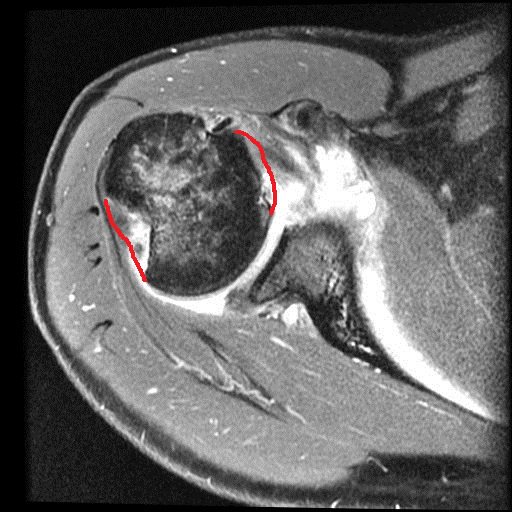

Nonetheless, as welfare science likes to term it, it’s entirely “a life worth living”. I have to pick my battles more than I used to, and I’ve had to learn to take more time to get exercise, rest, and avoid the stresses (or even unpleasant people) that can cause my health to take rapid downward spirals. I’m more fragile in many ways, such as having to stop doing karate because my shoulders have weakened. Here’s some interesting anatomy for you from a recent MRI scan of my right shoulder:

My left shoulder in top cross-sectional view, with the missing parts of my humeral head crudely outlined in red. There's more amiss here, too.

My left shoulder in top cross-sectional view, with the missing parts of my humeral head crudely outlined in red. There’s more amiss here, too.

My seizures cause my shoulder flexors to spasm, raising my arms up and crushing my humerus against my glenoid cavity of my scapula and causing occasional dislocations that abrade the humerus against the rim of the glenoid. The result, after numerous seizures, has been the wearing away of the articular cartilage of my shoulder and then the crumbling of the bony head of my humerus. Thus, once my NHS surgeon is ready to in coming months, I am due to have my coracoid process of my scapula cut off and moved, with its attached muscles and ligaments, to be screwed into the front of my glenoid cavity, bracing my humeral head more tightly against the glenoid and thereby resisting future dislocations. Luckily that operation can be done with several small incisions and endoscopy; invasive as the surgery is; thus recovery time won’t be so long.

Latarjet surgery (view of right shoulder joint [glenoid] from front): coracoid process moved posteroventrally. More details (w/videos) here.

It amuses me that all of this intense surgery looming on the horizon doesn’t worry me. I just want it done. I’ve been through a comparable surgery with my left shoulder, involving screwing my greater tuberosity back onto my humerus, so I know what recovery is like, and now that shoulder is doing fine. All that aside, my physical integrity has declined and I feel it every day. I may never return to my karate classes and earn that black belt I was seeking as a life-goal, but time will tell. I am trying to do what I can to remain as strong as I can for as long as I can.